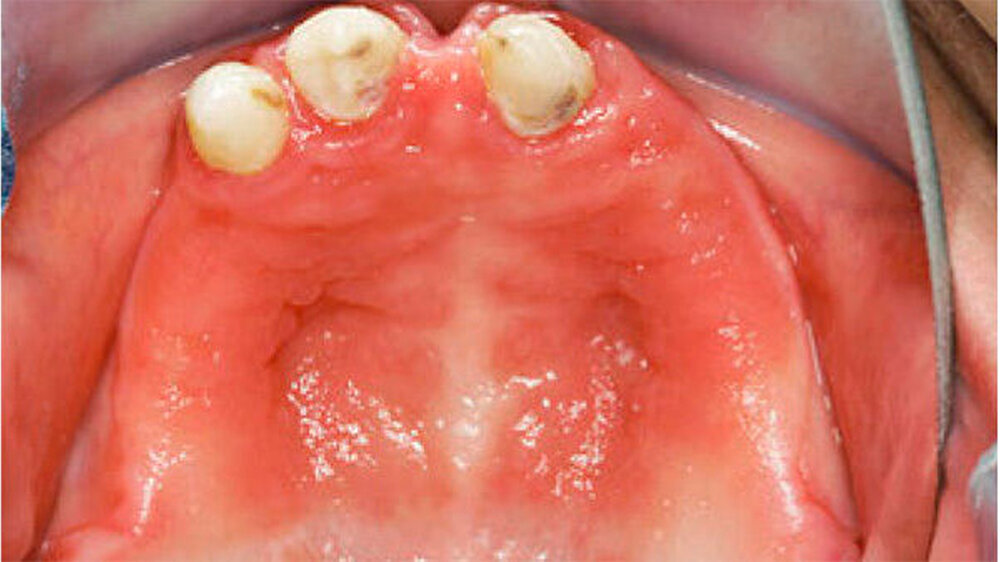

Bei dieser bei Behandlungsbeginn 16-jährigen Patientin waren seit Geburt nur die beiden ersten Molaren im Oberkiefer ausgebildet. Die Folge waren schmale und niedrige Alveolarkämme mit einem flachen Gaumengewölbe (Abb. 16 und 17). Die röntgenologische Abbildung bestätigte das geringe vertikale Knochenangebot. Eine Formanomalie der Zahnwurzeln ließ auf taurodonte Molaren schließen. Beide Molaren wiesen ausgedehnte kariöse Läsionen auf (Abb. 18).

Aufgrund des anatomisch sehr ungünstigen Prothesenlagers war der Erhalt der Restbezahnung im Oberkiefer anzustreben. Nach Kariesexkavation und Wurzelkanalbehandlung konnten beide Zähne mit einer Wurzelstiftkappe versorgt und die alten Prothesen entsprechend umgebaut werden. Im Anschluss an die Meisterabformungen und an die Ausrichtung der Wachswälle wurden die Modelle schädelbezogen einartikuliert, und die Prothesenzähne nach ästhetischen und funktionellen Richtlinien aufgestellt. Eine bilateral balancierte Okklusionsbeziehung konnte umgesetzt werden. Im Oberkiefer wurde eine gerüstverstärkte Totalprothese hergestellt, die auf den beiden Wurzelstiftkappen 16 und 26 verankert war. Im Unterkiefer konnte die Patientin mit einer Totalprothese versorgt werden (Abb. 21 bis 23).